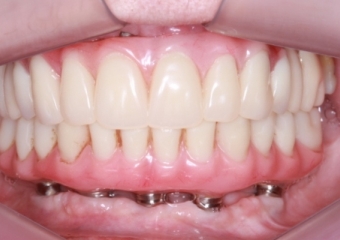

Implantes inferiores e prótese provisória inferior em Junho de 2014 - Clínica Cliniface

Implantes inferiores e prótese provisória inferior em Junho de 2014